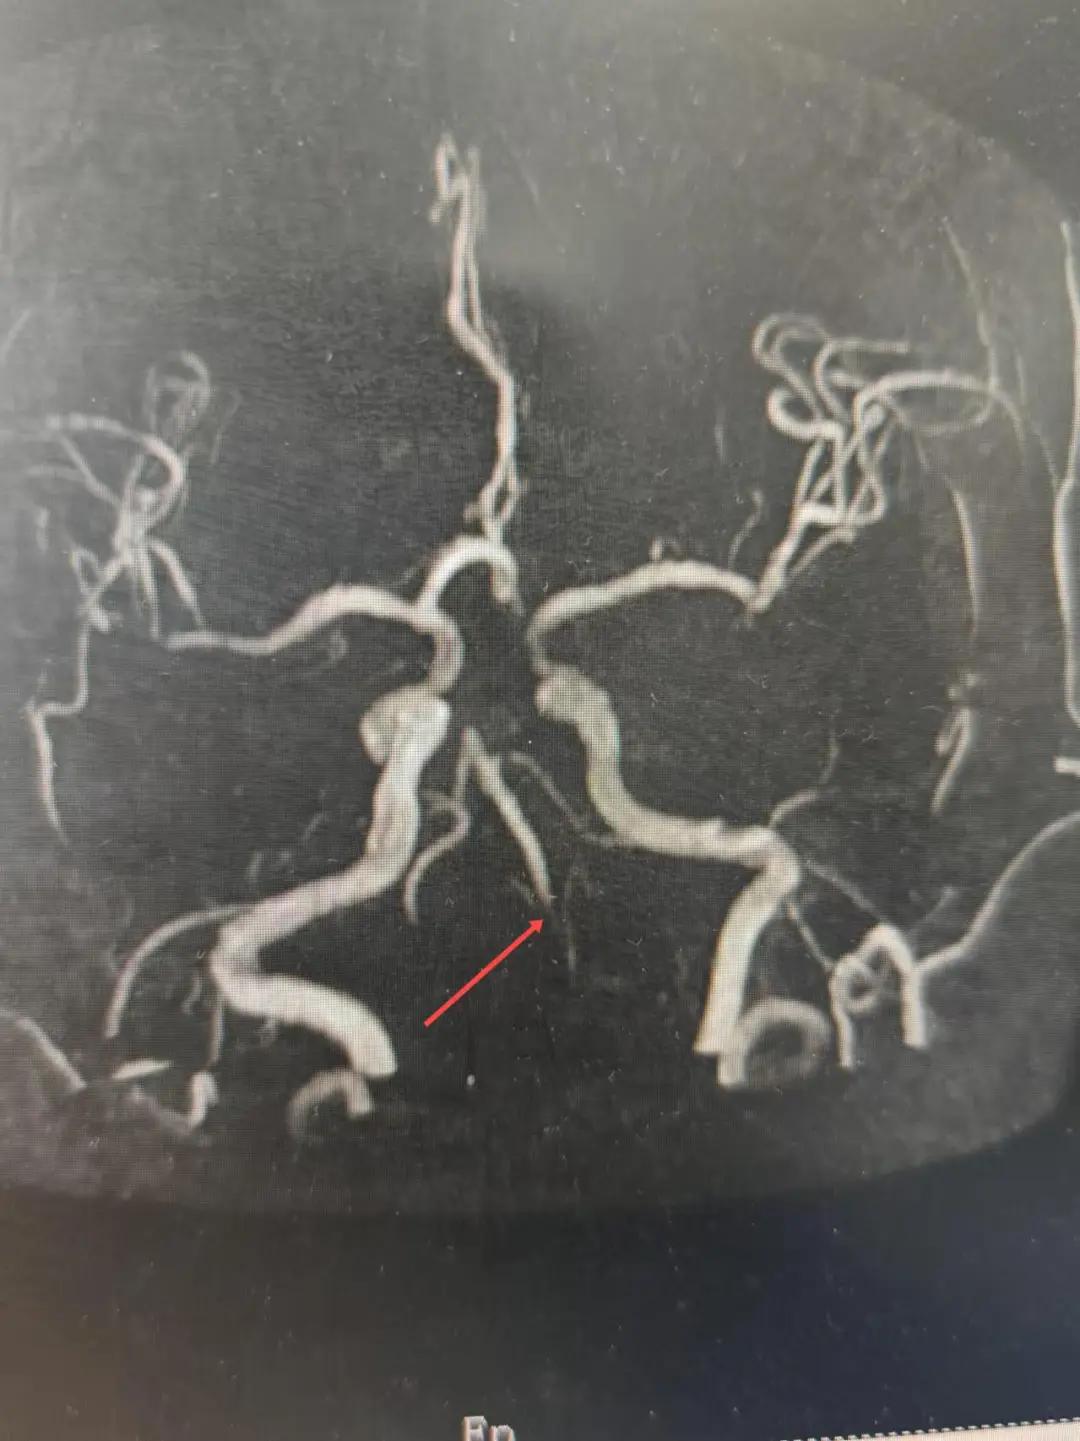

磁共振MRA提示基底動脈閉塞

在經(jīng)造影后,主刀醫(yī)生腦一科副主任楊慶堂發(fā)現(xiàn)患者基底動脈下段重度狹窄且狹窄段以遠(yuǎn)有大負(fù)荷血栓,其狹窄處考慮為動脈夾層,手術(shù)難度及風(fēng)險較大。楊慶堂副主任在彭壯副主任醫(yī)師的協(xié)助下運用spaceman(太空人)技術(shù),中間導(dǎo)管抵近血栓抽吸配合支架拉栓,成功開通血管。再次造影可見基底動脈管腔明顯增寬,遠(yuǎn)端血管顯影良好,且等待20分鐘后造影仍顯示血流通暢。楊慶堂副主任考慮到本次手術(shù)時間不宜過長,現(xiàn)患者基底動脈及分支前向血流維持良好,給予其抗栓藥物應(yīng)用后結(jié)束手術(shù),并建議患者3個月后復(fù)查造影,明確其基底動脈夾層情況。

造影可見血管夾層和大量血栓形成

取栓后血管管腔增寬,前向血流良好